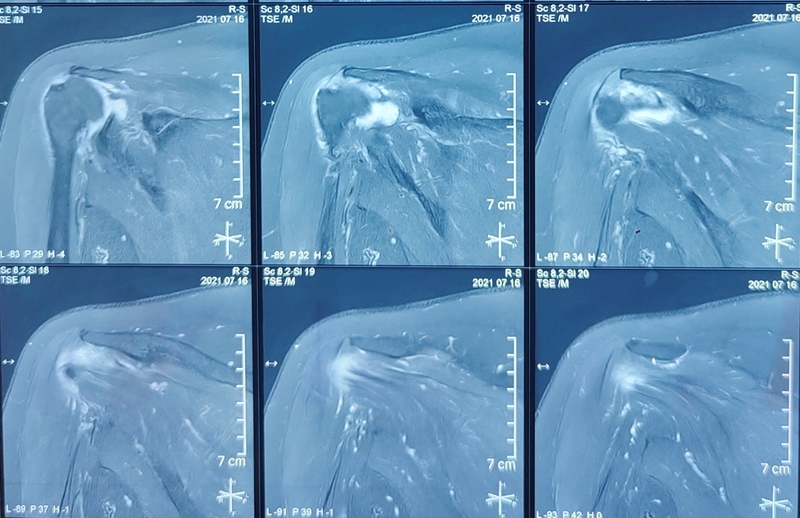

65岁女性,无明显诱因出现右肩疼痛、活动受限1年,外伤后加重2个月入院。术前右肩典型“假性瘫痪”,功能状态如图所示:

图GIF1~4

术前影像学检查示肱骨头向上移位,关节盂、肩峰和肱骨头退行性改变,典型肩袖撕裂性骨关节病(CTA)改变。

术后1年

图GIF5~7